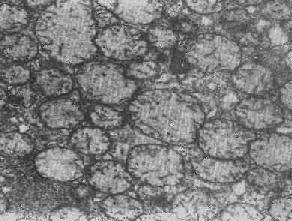

肾小管上皮细胞线粒体部分空泡变

图1-10肾小管上皮细胞线粒体部分空泡变

线粒体肿胀(基质型)空泡变(心肌缺氧)

图1-11 线粒体肿胀(基质型)空泡变(心肌缺氧)

2.大小改变 细胞损伤时最常见的改变为线粒体肿大。根据线粒体的受累部位可分为基质型肿胀和嵴型肿胀二种类型,而以前者为常见。基质型肿胀时线粒体变大变圆,基质变浅、嵴变短变少甚至消失(图1-9)。在极度肿胀时,线粒体可转化为小空泡状结构(图1-10,图1-11)。此型肿胀为细胞水肿的部分改变。光学显微镜下所谓的浊肿细胞中所见的细颗粒即肿大的线粒体。嵴型肿较少见,此时的肿胀局限于嵴内隙,使扁平的嵴变成烧瓶状乃至空泡状,而基质则更显得致密。嵴型肿胀一般为可复性,但当膜的损伤加重时,可经过混合型而过渡为基质型。